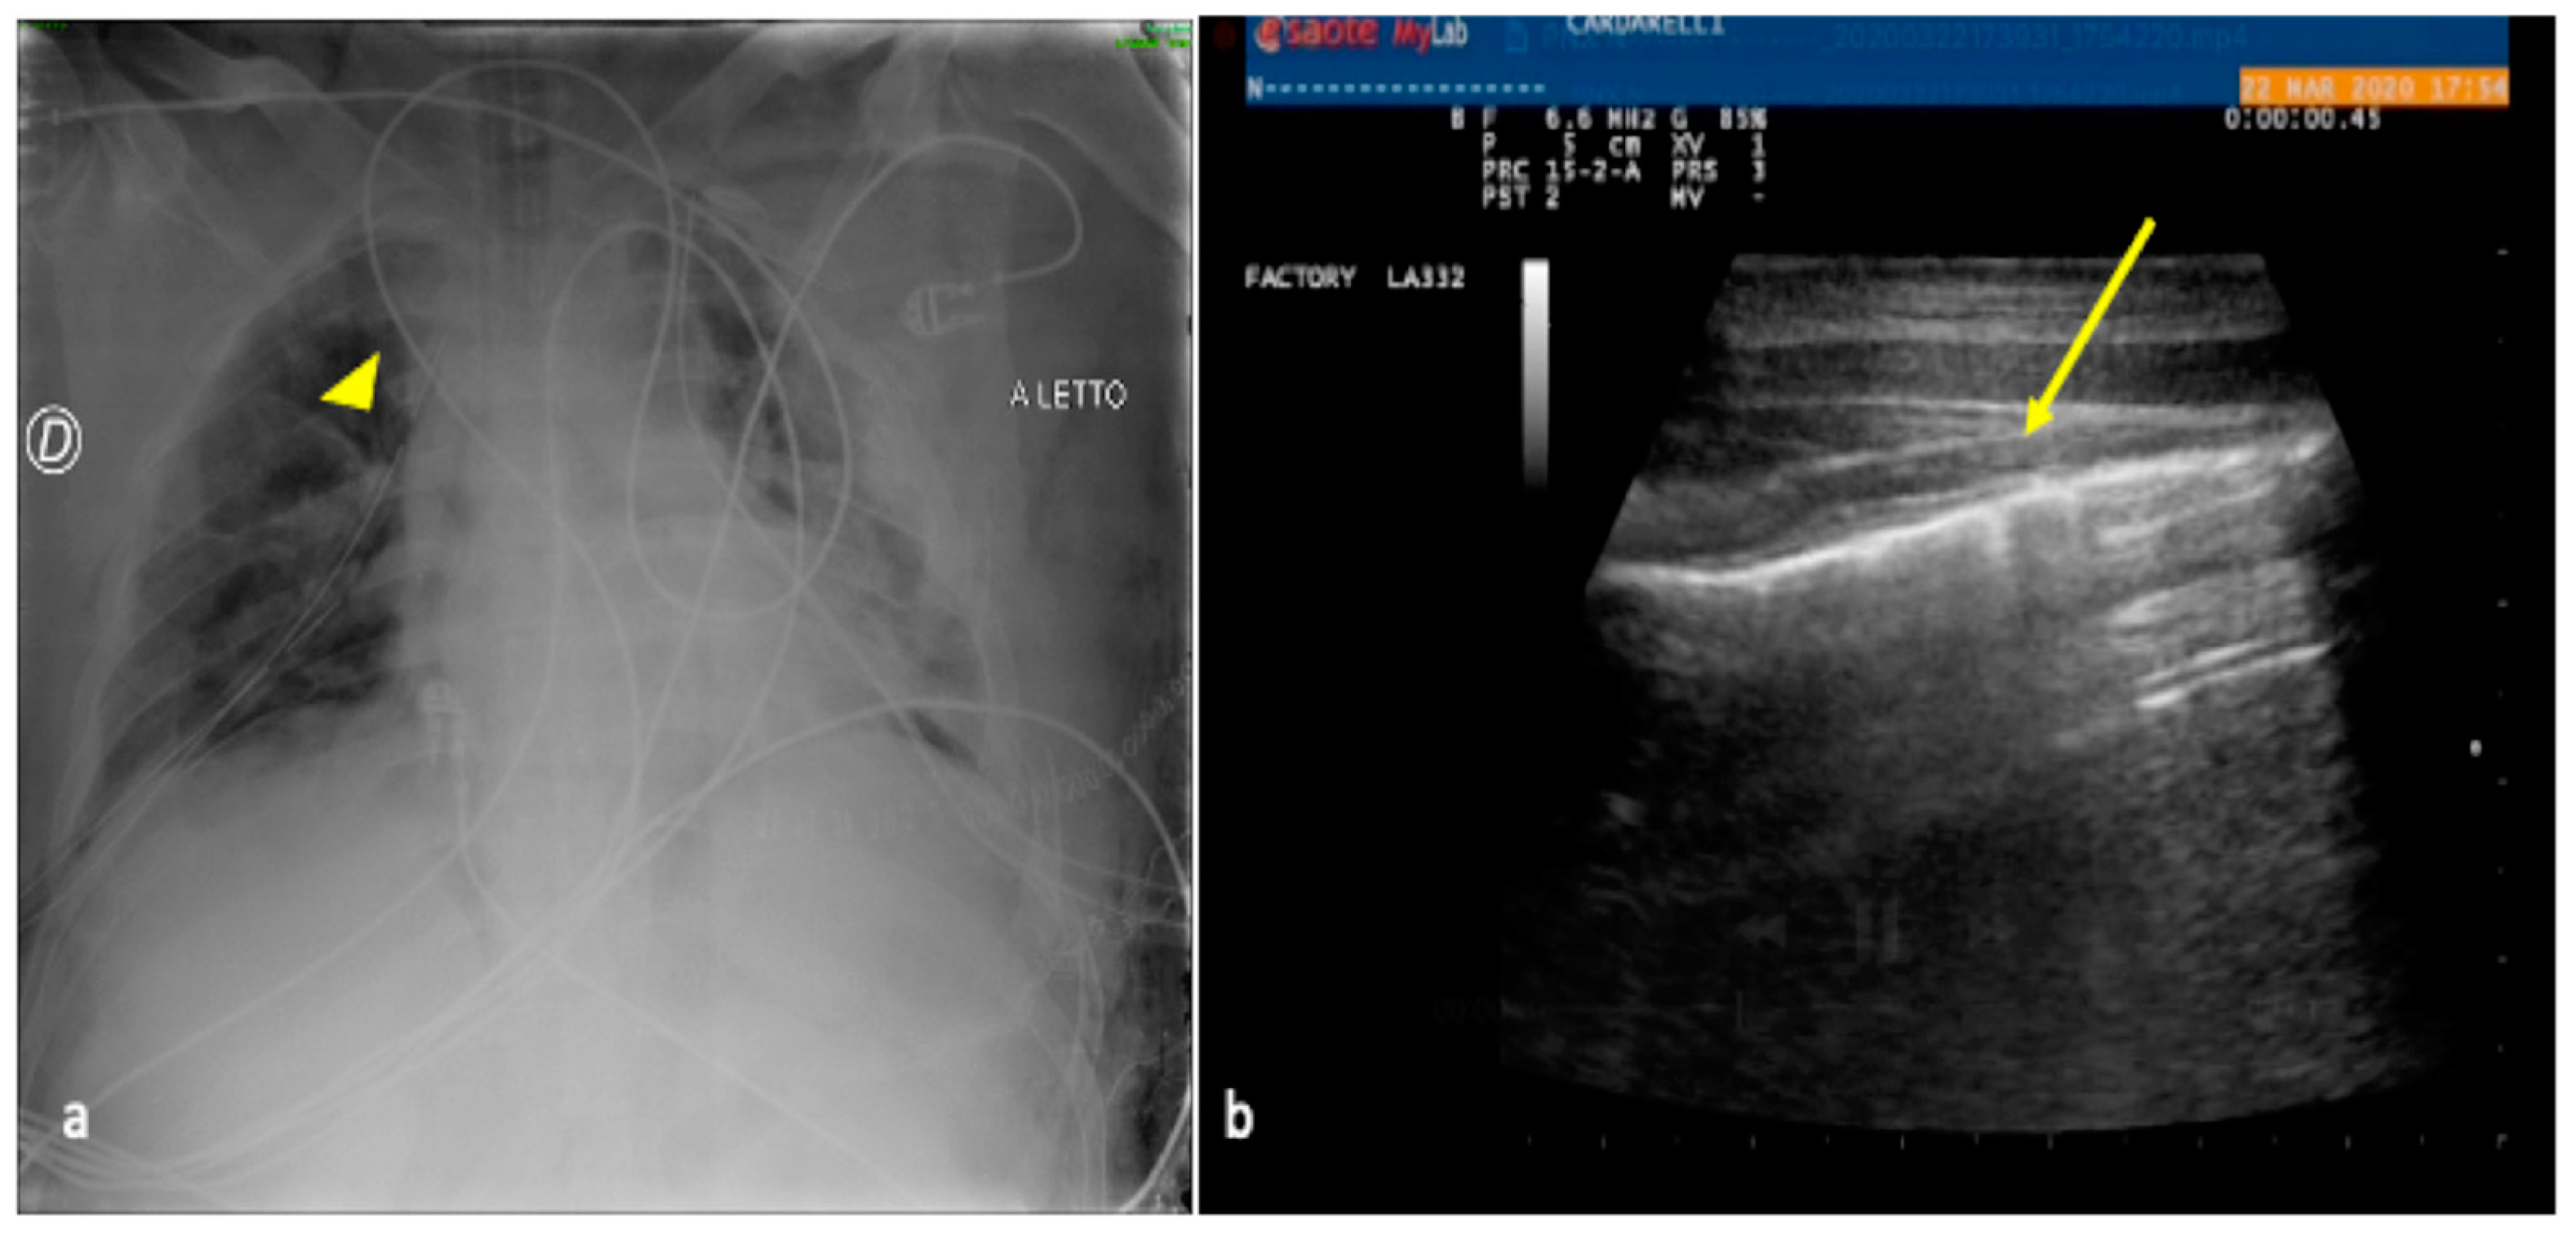

Figure 3.

A 30-year-old male patient admitted to the ICU for motor vehicle crash polytrauma resulting in multiple costal fractures and coma status. Bedside CXR (a) and LUS (b,c). (a) The CXR showed a blurred opacity in the left inferior pulmonary field (star); the basal field of the right lung appeared normally expanded (arrowhead). (c,d) LUS diagnostic integration performed on the same day showed a fluid collection in the basal region of the right lung indicating the presence of a small pleural effusion (b, arrowhead) that was not clearly demonstrable in the bedside CXR and also an inhomogeneous hypo-echogenicity indicating a parenchymal consolidation in the basal region of the left lung without fluid collection (c, star).